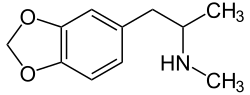

Amphetamines have an effect on norepinephrine levels similar to that of cocaine in that they both increase NE levels in the brain.[29] Amphetamine-like drugs are substrates for monoamine transporters, include NET, that cause a reversal in the direction of neurotransmitter transport.[17][30] Amphetamines cause a large accumulation of extracellular NE.[29] High levels of NE in the brain account for most of the profound effects of amphetamines, including alertness and anorectic, locomotor and sympathomimetic effects.[29] However, the effects that amphetamines have on the brain are slower but last longer than the effects cocaine has on the brain.[29] MDMA (3,4-Methylenedioxymethamphetamine or "ecstasy") is an amphetamine with wide recreational use. A study reported that the NET inhibitor reboxetine reduced the stimulant effects of MDMA in humans, demonstrating the crucial role NET has in the cardiovascular and stimulant-like effects of MDMA.[31]

- Methylenedioxymethamphetamine (MDMA)